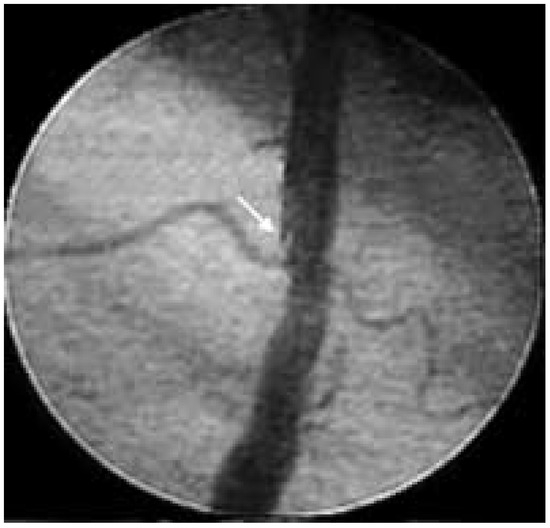

Angiography